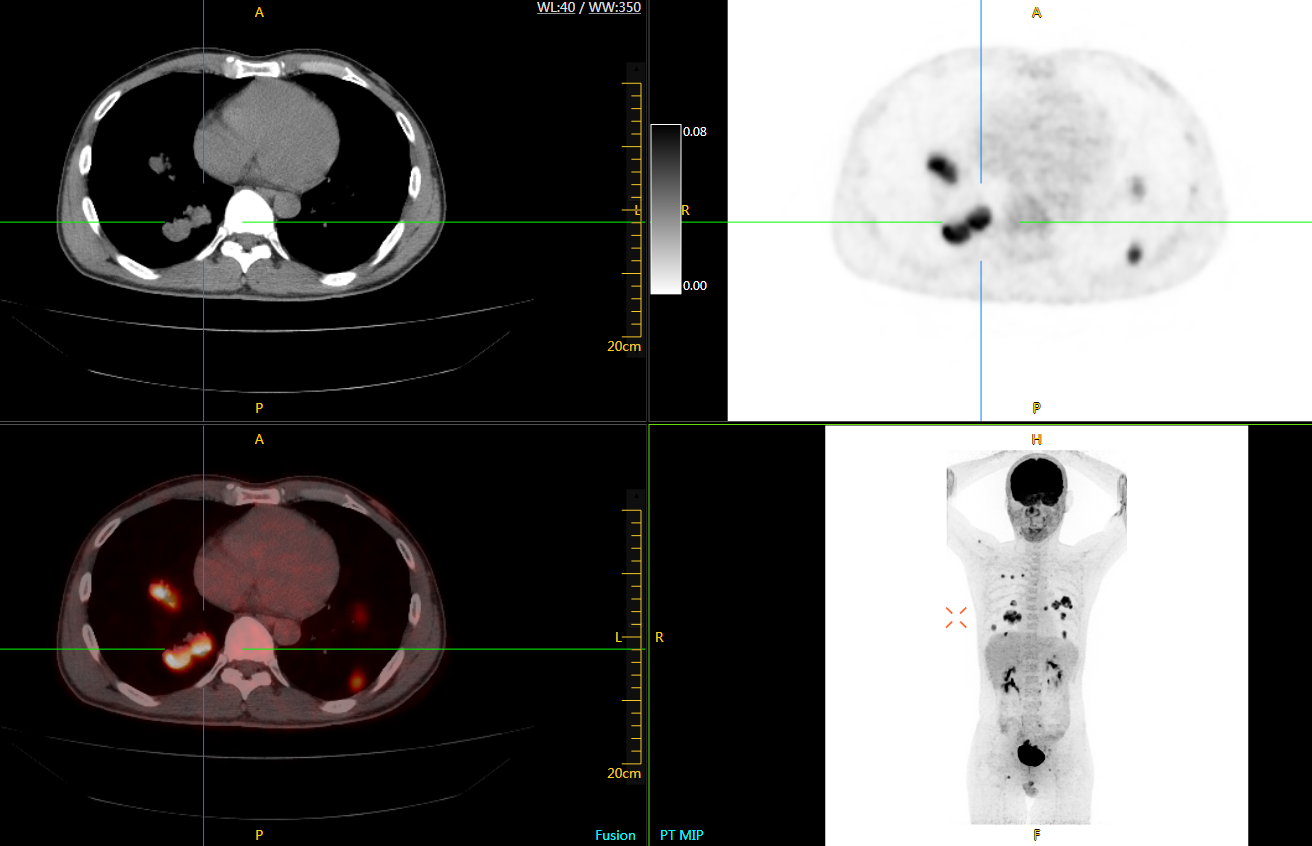

圖例

uExplorer探索者不再局限于傳統(tǒng)靜態(tài)代謝過程3D成像,而是在此基礎(chǔ)上新增一個維度——時間,從而實現(xiàn)4D全景成像。

注射總劑量為7.8mCi,14分鐘全身采集時間,在擁有超高靈敏度與超高分辨率的uEXPLORER上,即可得到展示顯示人體諸多精細(xì)結(jié)構(gòu)的高清三維圖像。

注射總劑量為7.8mCi,注射后1.6小時,基于uEXPLORER探索者掃描1分鐘的圖像

注射總劑量為0.67 mCi FDG(低于常規(guī)劑量的十分之一),基于uEXPLORER探索者掃描15分鐘的圖像

注射總劑量為6.9mCi,注射后10小時,基于uEXPLORER探索者掃描14分鐘的圖像